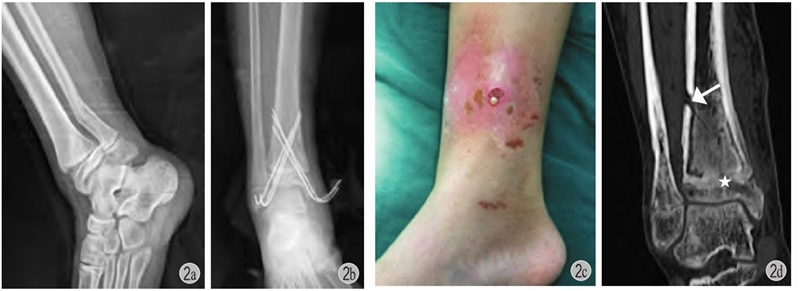

图2 患儿 男 11岁

a:右胫骨远端骨骺骨折(Salter-HarrisⅡ型)合并腓骨远端骨折;b:闭合复位,胫骨远端6枚克氏针贯通骺板固定;c:术后4个月见右小腿远端红肿,流脓;d:愈合后出现胫骨远端骺板早闭(星号)+局部皮质骨坏死(箭头)+慢性骨髓炎形成